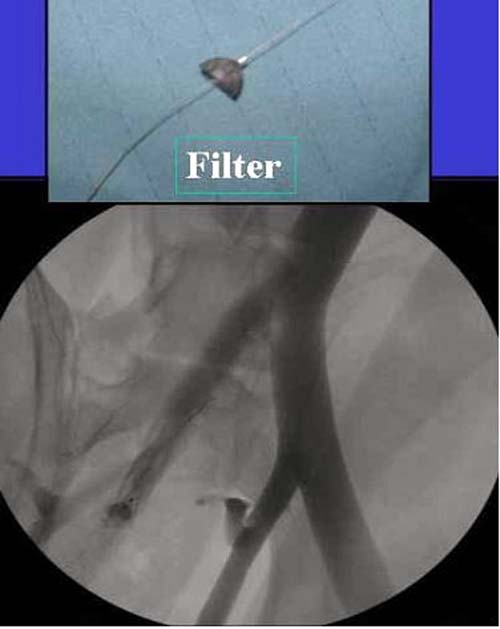

Работаем вместе с хирургами-травматологами (в штатах все травмированные больные поступают, как больные хирургической службы, ортопед выступает в качестве консультанта), т.е. мы даем рекомендации о проведении профилактики тромбоза, совместно решаем о проведении фильтра - вена кава фильтр (см. приложение).

Если вена кава фильтр, хирурги проводят эту процедуру, а медикаментозную профилактику назначаем сами.

Из лекарств: Lovenox, Heparin, Arixtra, Fragmin, каждый на свое усмотрение, почему-то общие хирурги предпочитают гепарин, хотя за последнее 6-7 лет кому не лень проводили исследования профилактики тромбоза, но к консенсусу не пришли, ортопеды-травматологи - Lovenox, Hip and knee reconstructive Surgeons - Arixtra, персонально считаю - кто с чем работает, тем и пользуются.

Продолжения антикоагулянта до условной активности больного, если больной самостоятельно передвигается с помощью костылей, считаю, можно решить о прекращении профилактики.